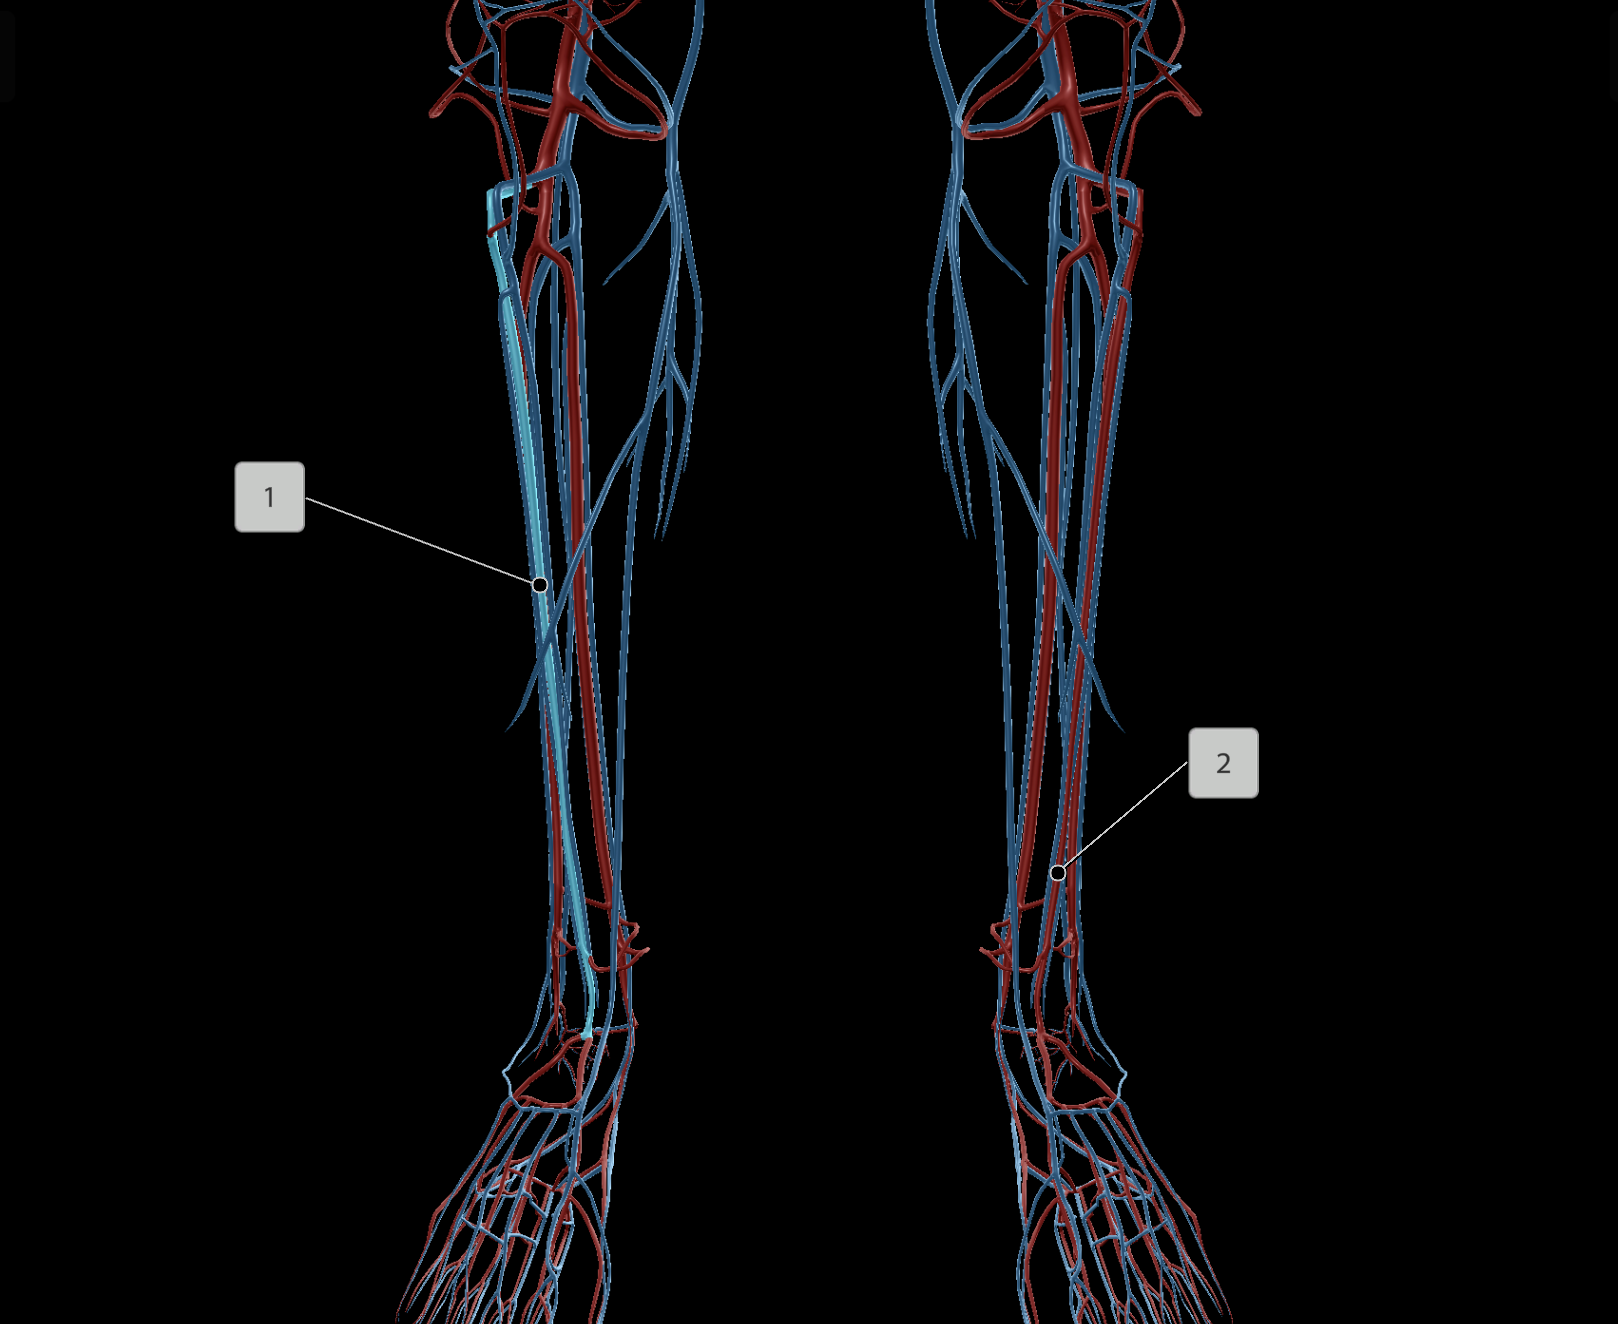

Anterior Tibial Artery

Posterior Tibial Artery

Femoral Vein

Popliteal Vein

Anterior Tibial Vein

Posterior Tibial Vein

Great Saphenous Vein

Deep Femoral Artery

Peroneal Artery